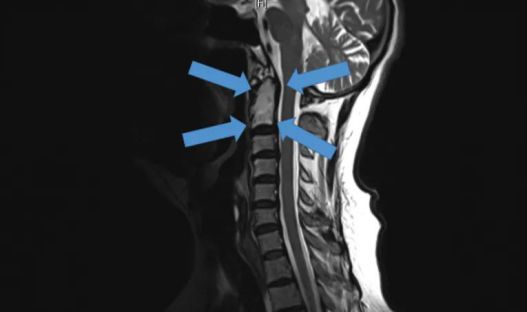

△2015年底,世界首例采用3D打印椎骨植入物

脊柱行業(yè)也是未來醫(yī)療器械市場,最新發(fā)展趨勢之一。通過3D打印技術(shù),來達到創(chuàng)新產(chǎn)品的目的,該技術(shù)可以促進骨骼向內(nèi)生長,并改善植入物對脊柱骨的固定,縮短制造流程,提高患者滿意度,從而在某些情況下更具成本效益。

例如,Medtronic鈦金屬3D打印平臺——TiONIC技術(shù)。使用激光方法制造具有增強表面紋理的植入物。Artic-L是該公司使用TiONIC技術(shù)制造的第一款金屬植入物。可供外科醫(yī)生在脊柱手術(shù)中使用。還有K2M的Lamellar,同樣采用鈦制造3D脊柱植入物。使用金屬3D打印技術(shù)特有的優(yōu)勢之一,可實現(xiàn)曾經(jīng)被傳統(tǒng)制造技術(shù),認為不切實際的結(jié)構(gòu)。